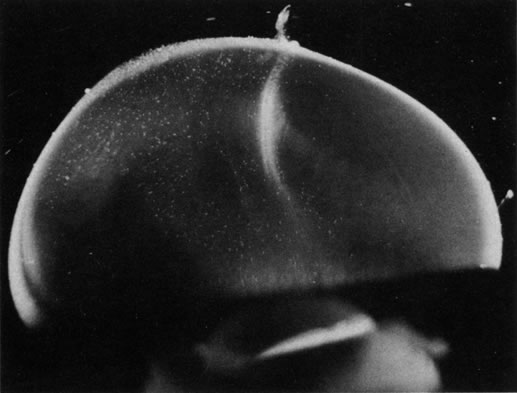

The retina is usually not involved in anterior PHPV. Indeed, previous studies have suggested that the anterior form is due to a primary defect in lens development and that vitreous changes are all secondary.34 This postulate has never been substantiated. There are rare instances of posterior PHPV in which opaque connective tissue arises from Bergmeister's papilla and persistent hyaloid vessels (Fig. 1).32,35 These can cause congenital falciform folds of the retina and, if severe, can cause tentlike retinal folds, leading on rare occasions to tractional and/or rhegmatogenous retinal detachment. Font and investigators36 demonstrated the presence of adipose tissue, smooth muscle, and cartilage within the retrolental plaque and suggested that PHPV arises from metaplasia of mesenchymal elements in the primary vitreous.